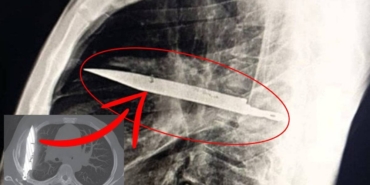

Feci Kaza: Genç Hayatını Kaybetti